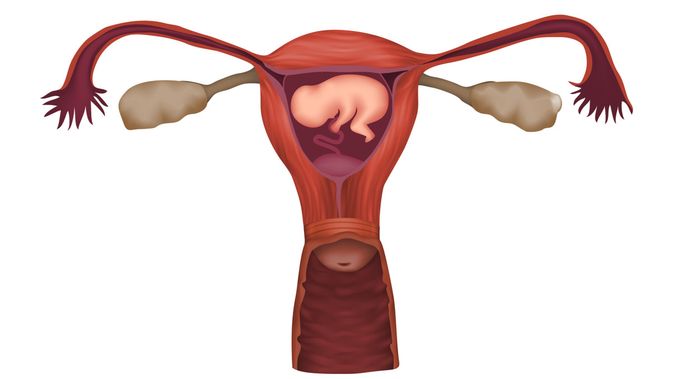

Perhatikan Letak Plasenta Janin Saat Hamil

Perhatikan Letak Plasenta Janin Saat Hamil

Apa Itu Plasenta? Ini Fakta yang Perlu Diketahui Seputar Ari-Ari Bayi

Apa Itu Plasenta? Ini Fakta yang Perlu Diketahui Seputar Ari-Ari Bayi

10 Fakta Menarik Plasenta pada Ibu Hamil - Ibupedia

10 Fakta Menarik Plasenta pada Ibu Hamil - Ibupedia